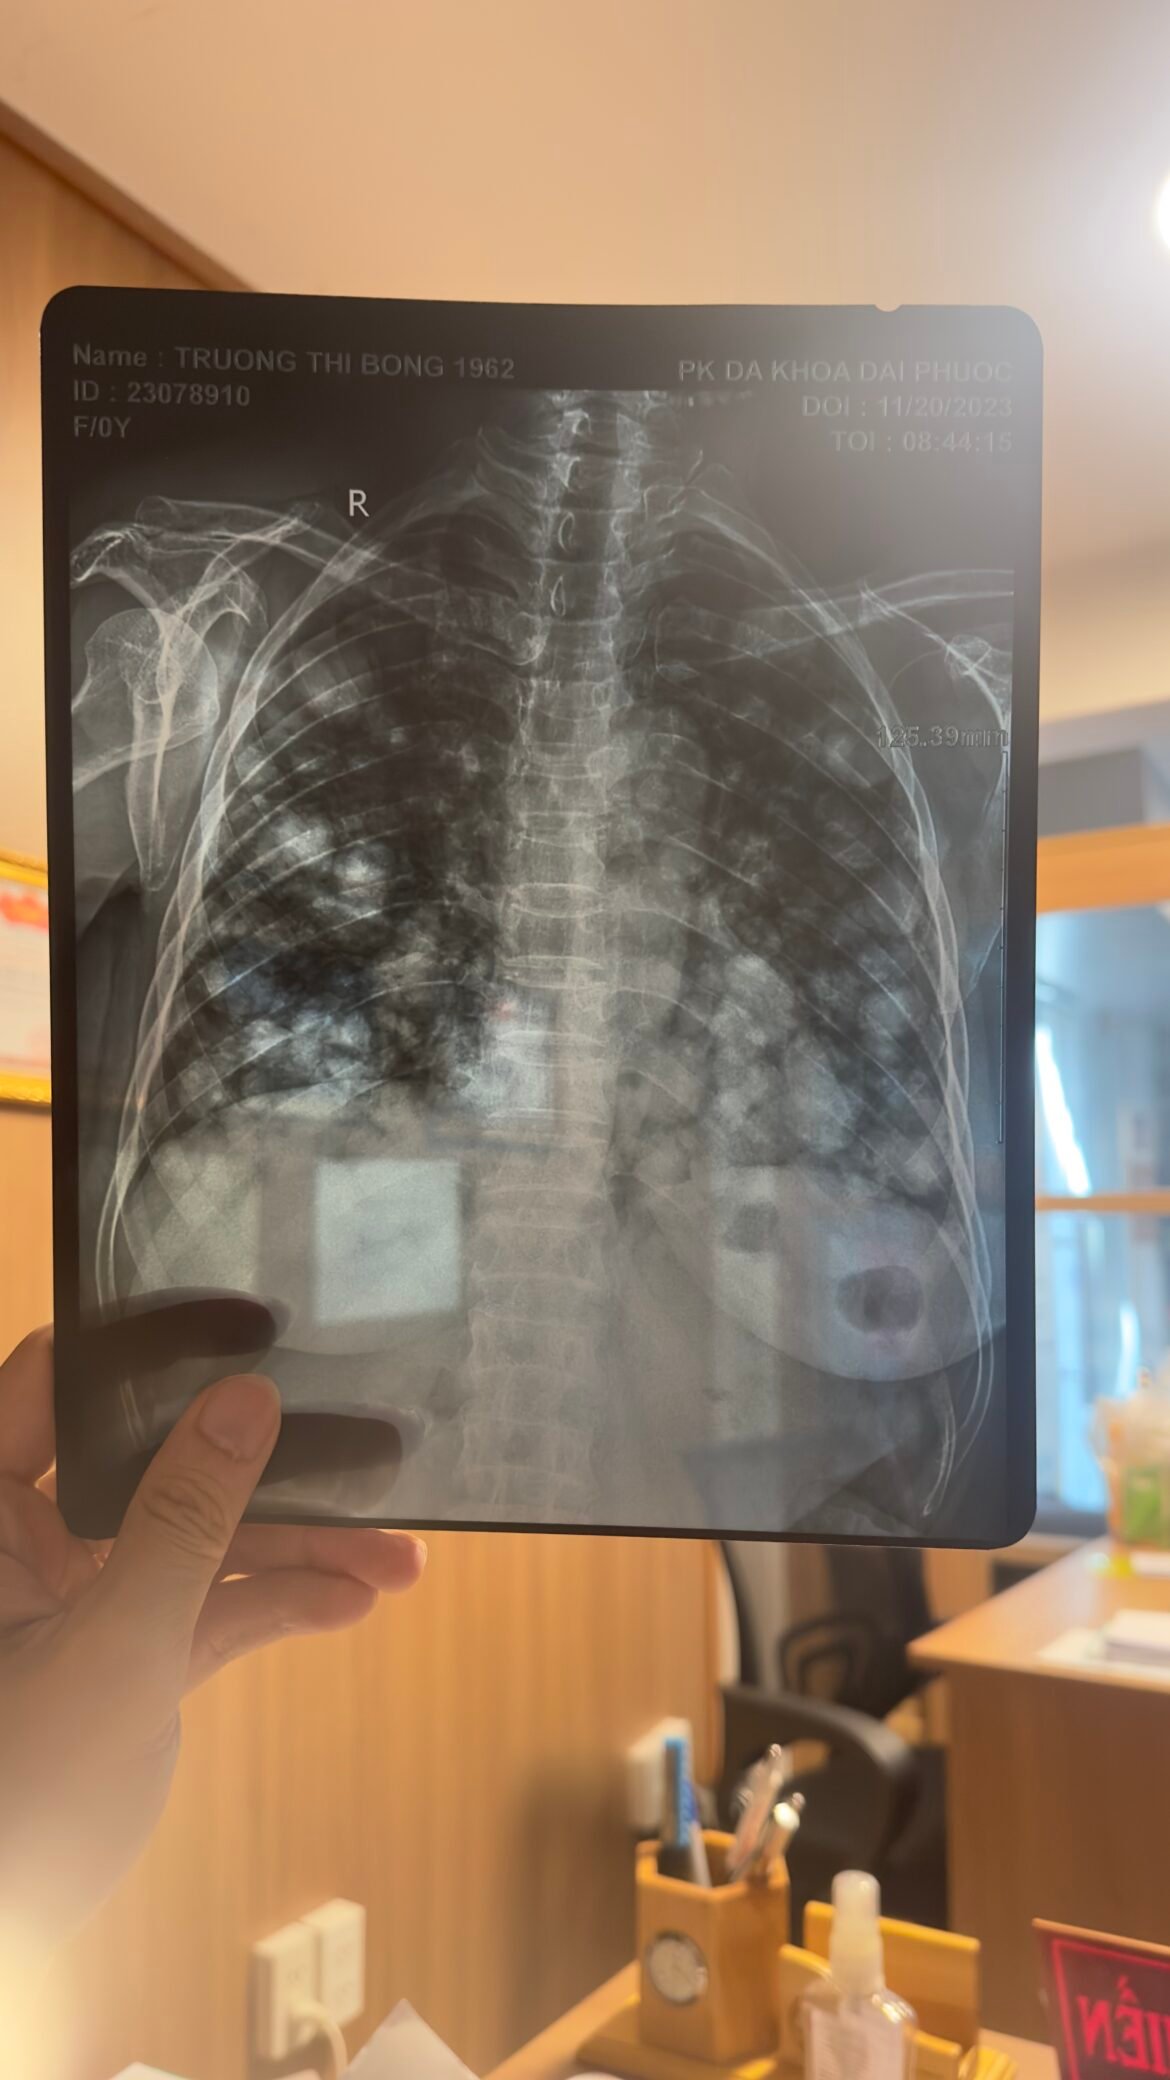

Bác sĩ nhìn phim phổi mà thấy xót xa trong lòng.

Đây là hình ảnh phim phổi mà trong y khoa gọi là bong bóng bay tử thần.